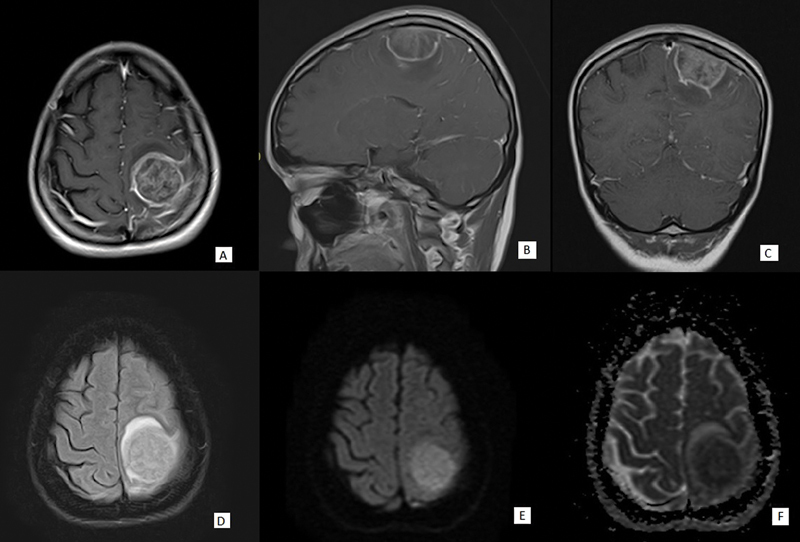

Objective  Meningiomas are the most common extra-axial tumors of the central nervous system. Meningiomas are particularly problematic when they invade deep or vital structures, causing the tumors to be inoperable. Nonsurgical adjunctive or salvage treatments to shrink a meningioma with multiple recurrences, located in deep-seated area or surgically unfit area, remain underexplored. The authors report a rare case of a spontaneously necrotic meningioma (World Health Organization [WHO] grade I) in a patient with systemic lupus erythematosus on chronic methotrexate and hydroxychloroquine. Case Study  A 29-year-old female with systemic lupus erythematosus had been treated with methotrexate and hydroxychloroquine for 7 years. She presented with episodes of seizures and hemiparesis. Neuroimaging revealed a possible necrotic meningioma in the left parietal parasagittal area. Subsequent intraoperative findings showed lytic tissue of the tumor, and by histopathology results the tumor was classified as WHO grade I with massive necrosis. After craniotomy with tumor removal, the patient's motor function fully recovered without recurrent seizures. Discussions  Necrotizing of small and benign meningioma is rarely found but otherwise interesting. The cause of this phenomenon is not yet understood thoroughly. In this case, we suspected various possible causes such as vasculitis interrupting blood supply, use of immunosuppressive drugs such as hydroxychloroquine or methotrexate, or, less likely, latent infections in the immunocompromised patient. Despite the lack of more evidence supports, this finding encourages further study of nonsurgical or salvage treatment of inoperable meningioma, so sequalae after refractory recurrences of meningioma can be prevented, and patient treatment outcomes can be improved.

Abstract Image